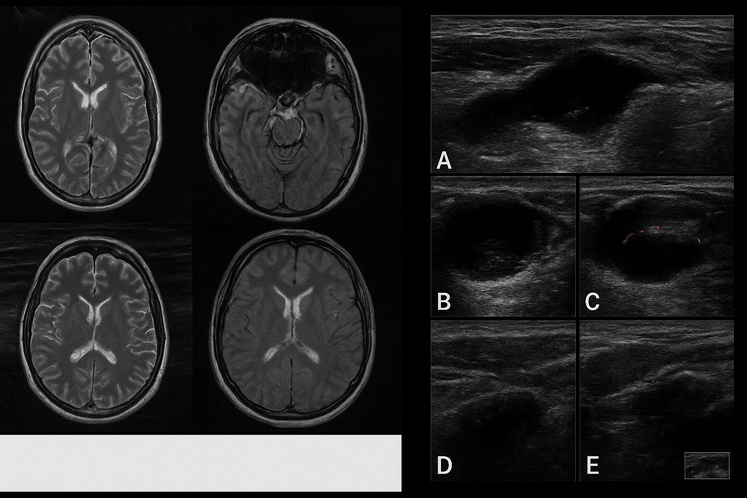

1. L’IRM « black-blood » pour les vascularites

Un des temps forts de cette édition sera la session intitulée Radiology Bootcamp prévue le 25 octobre, consacrée à l’imagerie des maladies auto-inflammatoires. Parmi les thèmes abordés : l’utilisation de l’IRM « black-blood sequencing » qui permet de mieux visualiser la paroi des gros vaisseaux chez les patients atteints de vascularites.

Toujours dans la même session, un cours intitulé Axial Imaging in Inflammatory Arthropathy : Distinguishing Degeneration from Disease met en lumière le défi suivant : différencier à l’imagerie les modifications « mécaniques/dégénératives » des signes d’« inflammation vraie ».

Concrètement, cela signifie pour le radiologue : adopter des séquences IRM ou échographiques plus sensibles à l’œdème osseux, à la synovite, mais aussi interpréter au-delà du cliché classique. Ce glissement ouvre la voie à une imagerie plus « rhumatologique » et spécialisée.